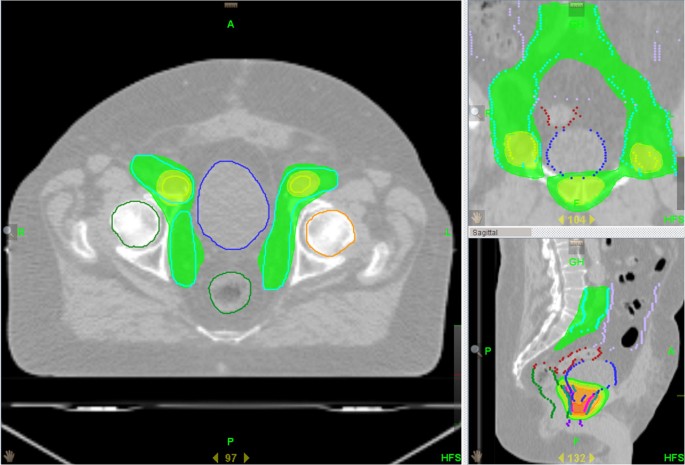

Salvage nodal radiation therapy is typically applied to patients who have already undergone radiotherapy in the past, for whom the recurrence of cancer within the lymph nodes signifies an evolving clinical scenario. The treatment involves several advanced techniques, each designed to maximize targeting accuracy while mitigating the risk to non-cancerous tissues.

The major methods used in SNRT include:

- Volumetric Modulated Arc Therapy (VMAT)

- Intensity-Modulated Radiation Therapy (IMRT)

- Stereotactic Body Radiation Therapy (SBRT)

- Intensity-Modulated Proton Therapy (IMPT)

Each method comes with its own set of subtle details and a range of considerations that the treating physician must weigh carefully. When these technologies are used in conjunction with PET imaging findings, the resulting treatment plan is finely tuned to offer the best possible outcomes. In many ways, SNRT represents a marriage between cutting-edge technology and a nuanced understanding of prostate cancer behavior, providing hope for those whose treatment options were previously limited.